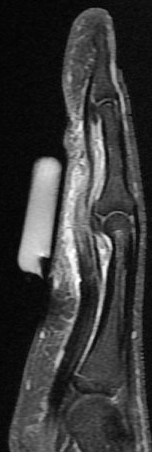

Figure 1 for case gout arthritis ( RID3567 )

Figure 1

Flexor tenosynovitis, tendon infiltration and also 2nd MCP synovitis with subtle reactive osteitis and early erosive change. My differential was RA vs gout. This is proven gout.